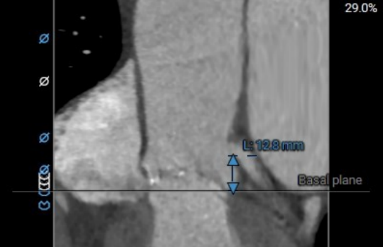

左冠高度:12.8mm

右冠高度:16.4mm

左冠瓣叶长度:17.8mm

右冠瓣叶长度:13.0mm